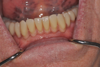

La mise place des vis de cicatrisations

3 mois après la pose des implants

2 temps chirurgicale. Pour que le patient puisse

avoir sa prothèse mobile pendant ces 3 mois